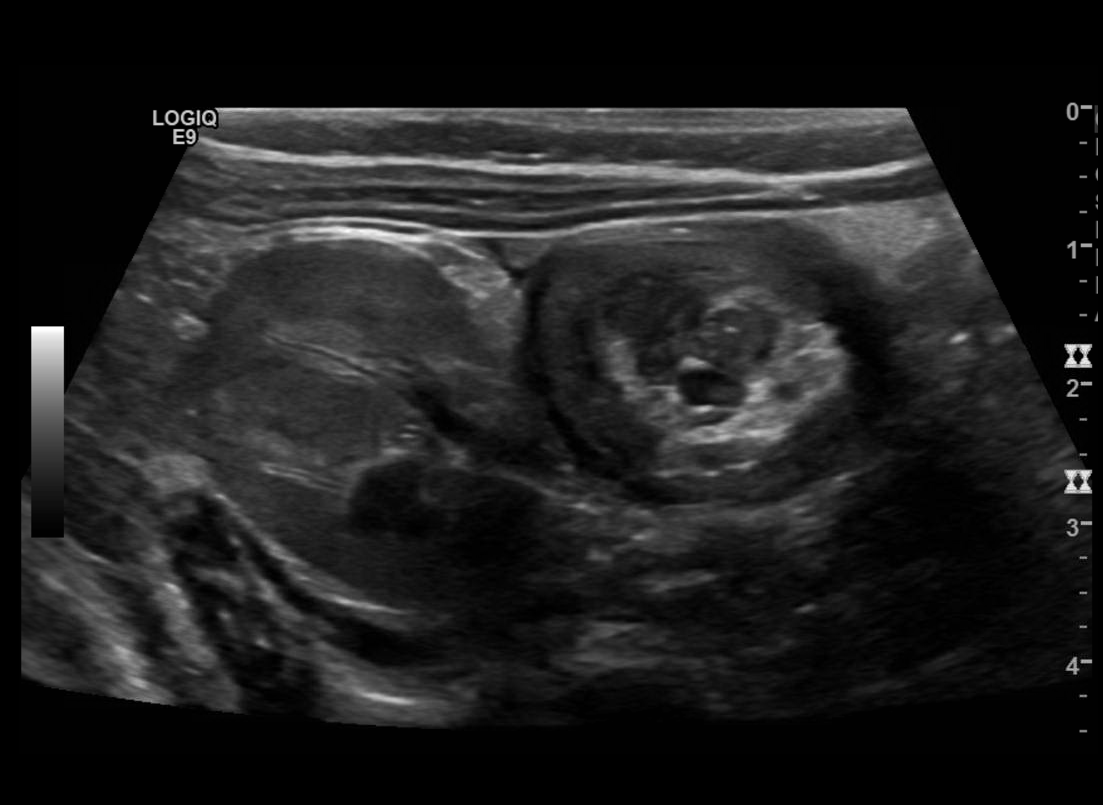

Intussusception